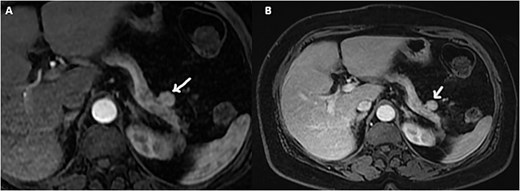

On the complementary CT scan, this lesion exhibits the same tissue characteristics and enhancement as the spleen (Fig. 2), along with its own vascularization through a distinct vascular pedicle (Fig. 3), which is more suggestive ‘of an accessory spleen than an insulinoma of the tail of the pancreas.’

Axial sections of an abdominal non-contrast CT scan (A) and in the arterial phase (B) reveal a nodule adjacent to the tail of the pancreas that is hypervascular on arterial phase and follows the same pattern of enhancement as the spleen.